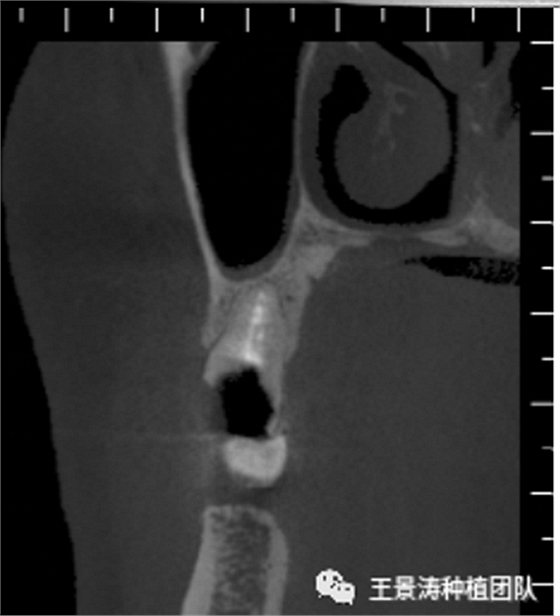

下述病例則是15區(qū)域的即刻種植,15因牙冠折斷于齦下,無法樁核冠修復(fù),則考慮種植修復(fù)。但拍攝CBCT后發(fā)現(xiàn)根尖距上頜竇底距離較短?;颊邽槟贻p女性,無全身系統(tǒng)疾病且可利用上頜竇底與根尖皮質(zhì)骨雙側(cè)皮質(zhì)骨固位,且此位置可通過頰側(cè)軟組織減張技術(shù)獲得嚴(yán)密封閉牙槽窩。因其根尖距上頜竇距離較低,遂拔除15后行上頜竇內(nèi)提升,埋入式種植,最終修復(fù)的完成。